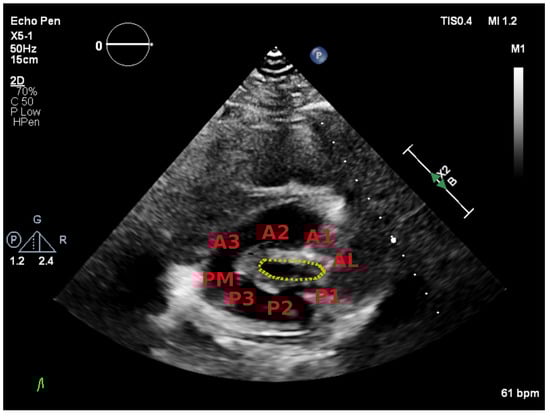

| Anterior Leaflet | Posterior Leaflet | |||||

| Thickness (0–6) (0 = normal, 1 = thickened) | A1 | A2 | A3 | P1 | P2 | P3 |

| Mobility (0–6) (0 = normal, 1 = limited) | 0–1 | 0–1 | 0–1 | 0–1 | 0–1 | 0–1 |

| Calcification (0–10) (0 = no, 1–2 = calcified) | 0–2 | 0–1 | 0–2 | 0–2 | 0–1 | 0–2 |

| Subvalvular Apparatus | ||||||

| Proximal Third | Middle Third | Distal Third | ||||

| Thickness (0–3) (0 = normal, 1 = thickened) | 0–1 | 0–1 | 0–1 | |||

| Separation (0–6) (0 = normal, 1 = partial, 2 = no) | 0–2 | 0–2 | 0–2 | |||